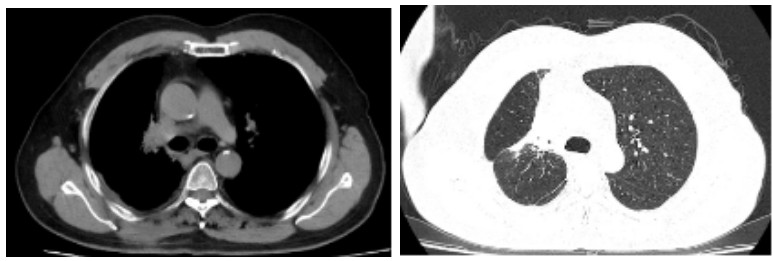

Figure 2. One year after carbon ion therapy for chest tumor